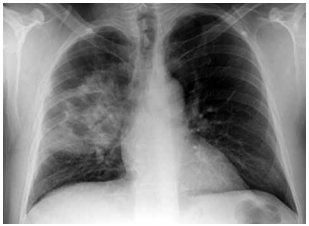

Porém, após a reposição volêmica, o paciente apresenta PA: 86 × 52 mmHg; FC: 116 bpm; saturação venosa de O2: 61%; lactato: 4,6 mmol/L (antes 4,9). Gasometria venosa: pH: 7,31; PvCO2: 46 mmHg; HCO3: 22 mEq/L. Creatinina: 2,2 mg/dL (baseline 1,0); bilirrubinas normais; leucócitos: 17.800/mm3; PCR: 22 mg/dL. Realizou-se a radiografia de tórax a seguir:

(Arquivo pessoal; imagem usada com autorização)